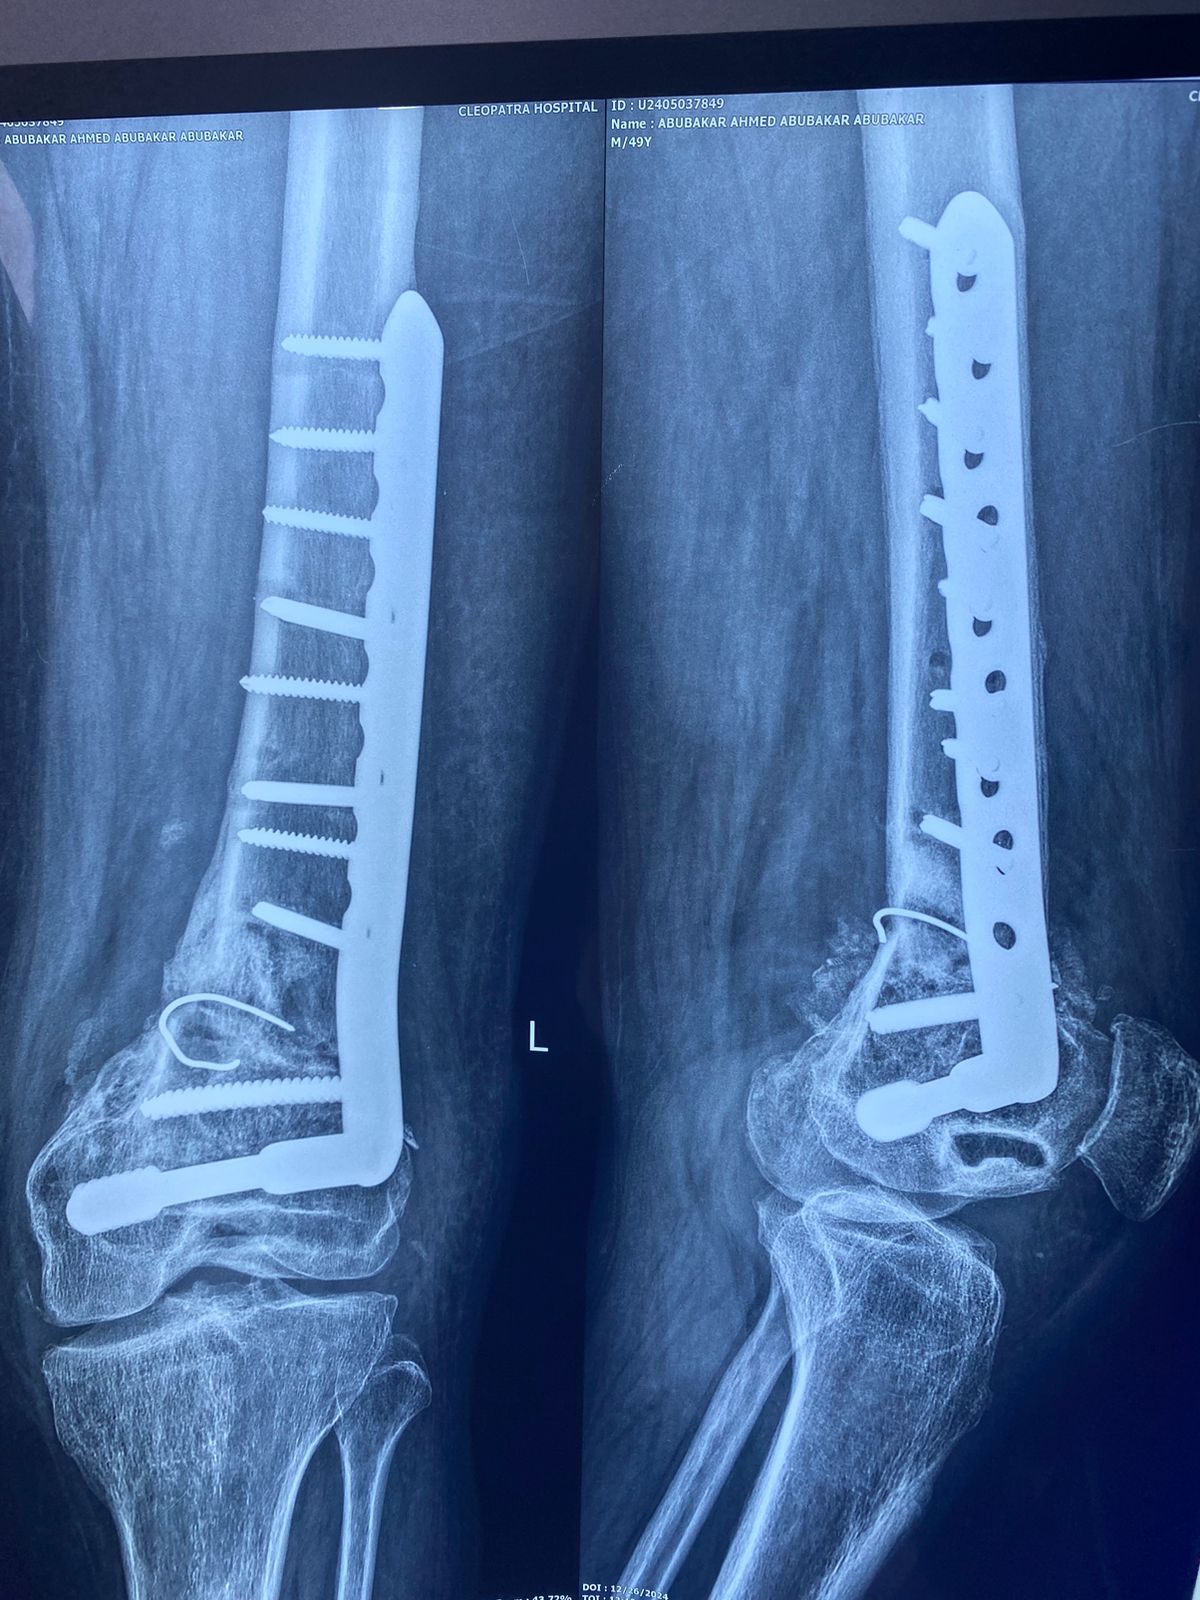

ابوبكر أبوبكر ( من نيجريا)

صورة اشعة تبين شريحة تم تركيبها بشكل خاطئ ترتب عليها اعوجاج بالركبة

الأشعات بعد الجراحة مباشرة و الاشعات الاخيره بعد الجراحة ب ٦ أشهر